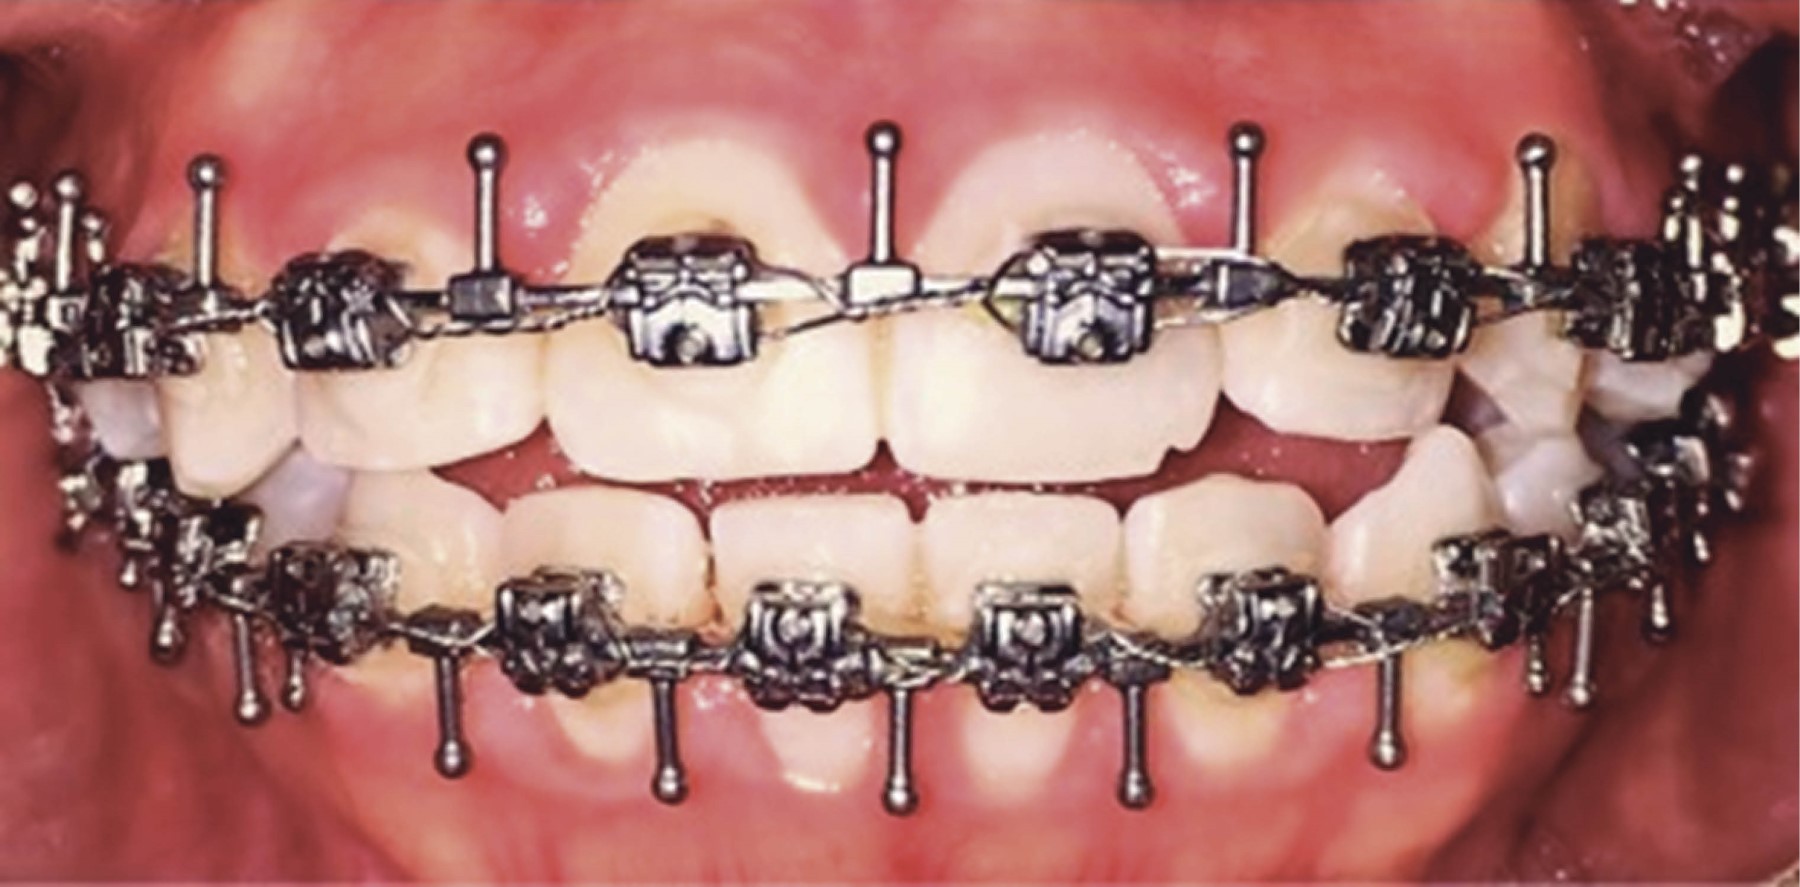

Introduction: currently, computer-aided planning of orthognathic surgery helps us obtain better results, avoiding errors that could occur with conventional orthognathic surgery planning. With virtual planning of orthognathic surgery, we obtain surgical guides that help us stabilize the maxillary segments during surgery to avoid recurrences. Currently, the use of cutting guides and customized plates in Le Fort I osteotomy eliminates the need for occlusal surgical guides, minimizing surgical time, making the surgery more agile, and improving results. Clinical case: a 20-year-old female patient was diagnosed with maxillary vertical excess and anterior open bite. Surgery was performed using virtual surgery to plan a 4 mm Le Fort I impaction osteotomy, using custom-made titanium plates and cutting guides during the procedure. Results: the advantages of using this management protocol in orthognathic surgery are: reducing pre- and intraoperative work time, minimizing errors in surgical movements, developing simpler and more precise surgical procedures, avoiding injuries to the anatomical structures involved, transferring the results of the virtual simulation in the manufacture of cutting templates to the operating room, obtaining highly satisfactory results, carrying out and establishing an optimization protocol and finally obtaining a database of surgical patients. Conclusions: it is a versatile technique, with a minimum degree of difficulty and easy to perform.

Figure 1